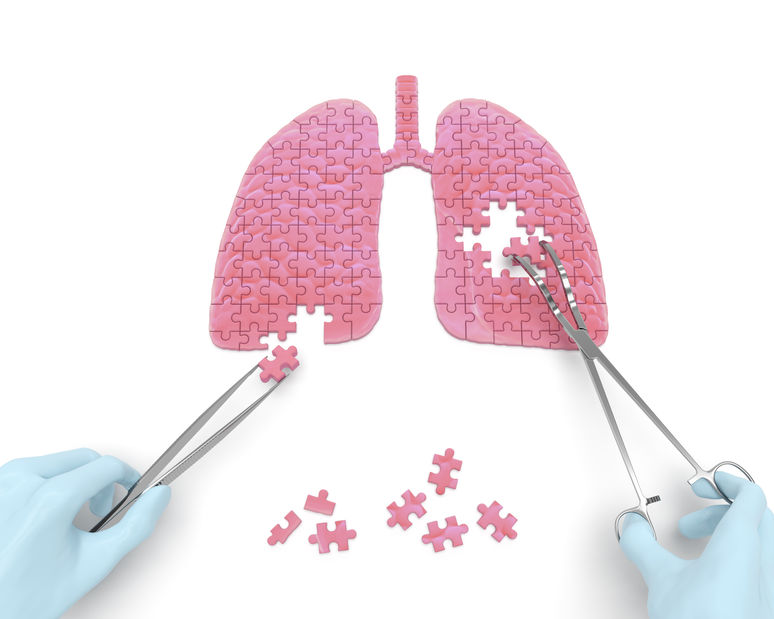

A pneumonectomia é uma cirurgia complexa e de grande porte, que consiste na retirada de um pulmão. Embora não seja a primeira alternativa dos médicos,